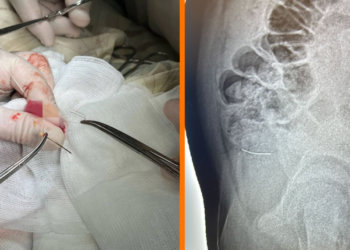

Врачи городской детской больницы Бийска прооперировали 13-летнего подростка, проглотившего корсажную иглу. Об этом сообщает пресс-служба медучреждения. Мальчик поступил в приёмное...